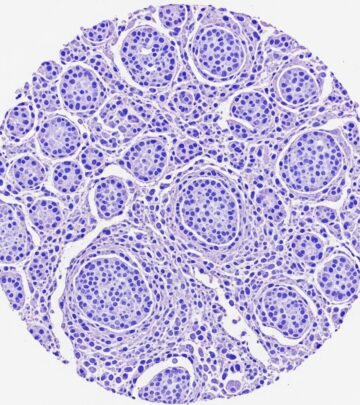

Paracoccidioidomycosis Pathology: Comprehensive Diagnosis Guide